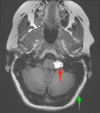

Both lipomas and dermoid cysts of the cerebellopontine angle are rare tumors. These tumors differ in their embryological origin but share similar features on imaging. Both of these congenital lesions can be found in the cerebellopontine angle (CPA), and symptomatic clinical presentation is dictated by the location of the lesion. This paper demonstrates a unique case in which a CPA lipoma was misidentified as a dermoid cyst, leading to surgical intervention. Further, the paper provides a literature review of CPA lipomas and dermoid cysts to aid readers in further differentiating between these two unique tumors.